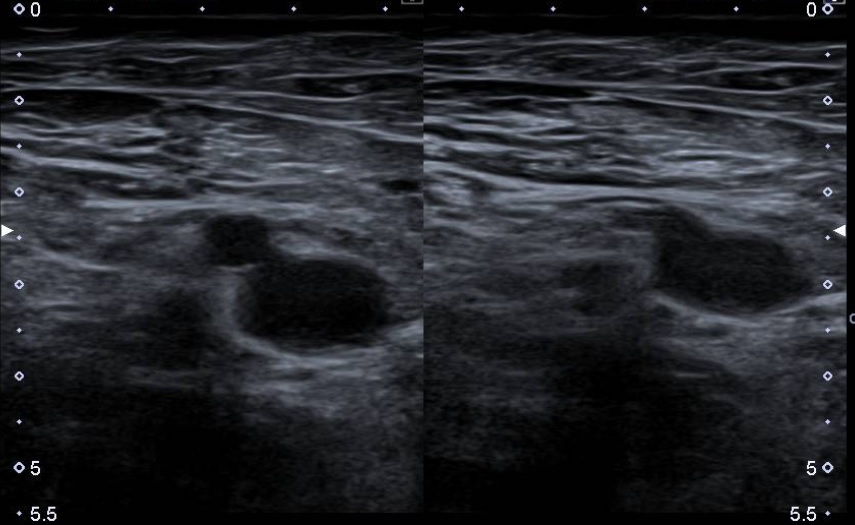

Ante elevación del dímero D, decidimos realizar ecografía clínica a pie de cama: Las venas femoral común, femoral profunda, cayado de la vena safena mayor y poplítea izquierdas no son compresibles con el transductor y no presentan vascularización en el estudio Doppler y se observa material ecogénico en su interior. Hallazgos compatibles con trombosis venosa profunda extensa.

Diagnóstico diferencial: celulitis o trombosis venosa. Parecía más probable la celulitis debido a la presencia de úlcera en región glútea ipsilateral, con reactantes de fase aguda elevados en la analítica y habiendo tomado correctamente la medicación anticoagulante. Sin embargo, la ecografía ayudó en el diagnóstico de trombosis venosa profunda extensa.